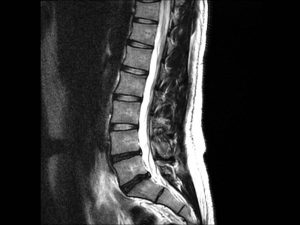

The Ontario government recently announced that they will begin consultations on a proposal to allow chiropractors to order advanced imaging like MRI, CT scans and diagnostic

We’ve recently been getting more questions about home traction devices for lower back pain. The goal of traction is to stretch the spine lengthwise to create